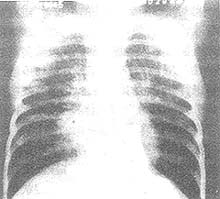

2.X线检查

X线形态与病情、病期有密切关系。肺纹理增厚、模糊为腺病毒肺炎的早期表现。肺部实变多在发病第3~5天开始出现,可有大小不等的片状病灶或融合性病灶,以两肺下野及右上肺多见。发病后6~11天,其病灶密度随病情发展而增高,病变也增多,分布较广,互相融合。与大叶肺炎不同之处是,本病的病变不局限于某个肺叶。病变吸收大多数在第8~14天以后。有时若病变继续增多、病情增重,应疑有混合感染。肺气肿颇为多见,早期及极期无明显差异,为双侧弥漫性肺气肿或病灶周围性肺气肿(图1)。1/6病例可有胸膜改变,多在极期出现胸膜反应,或有积液。

图1 腺病毒肺炎,肺气肿

3岁,女孩。持续高热咳喘8天,咽拭子分离出Ⅶ型腺病毒。X线胸片显示右肺门增密,两肺内带纹理增厚粗多,右肺内带片状阴影,两下肺透亮度明显增高,两膈位于第10后肋水平,膈面弧度变平,为重度肺气肿表现